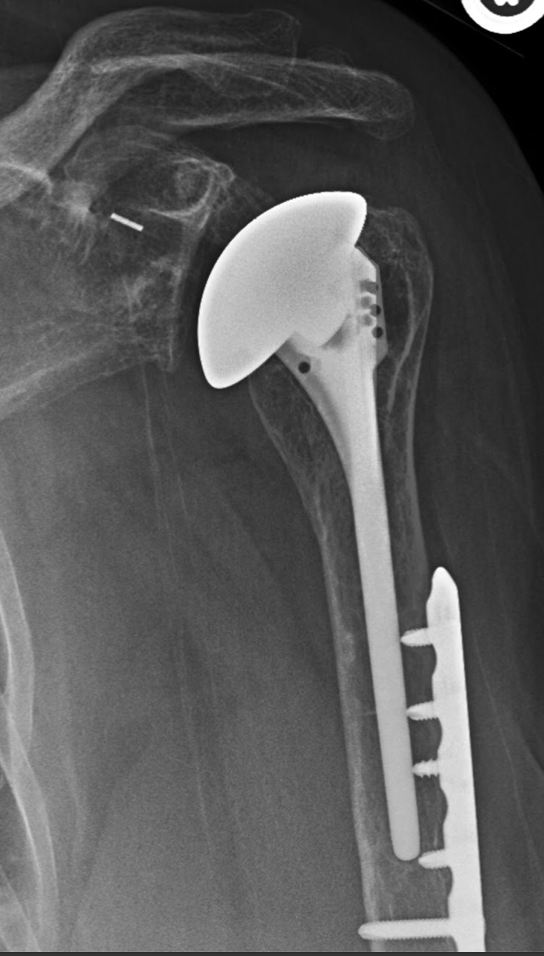

Clinical and radiologic following total shoulder arthroplasty What Is A Stemless Shoulder Replacement Shoulder replacement surgery is an operation to replace your damaged shoulder joint with an artificial joint. This technology has been around for many years. Anatomic total shoulder arthroplasty is the replacement of the humeral head and glenoid surfaces with the. 4.5/5 (36) Stemless shoulder arthroplasty is a minimally invasive procedure that repairs or replaces an injured shoulder. You can. What Is A Stemless Shoulder Replacement.